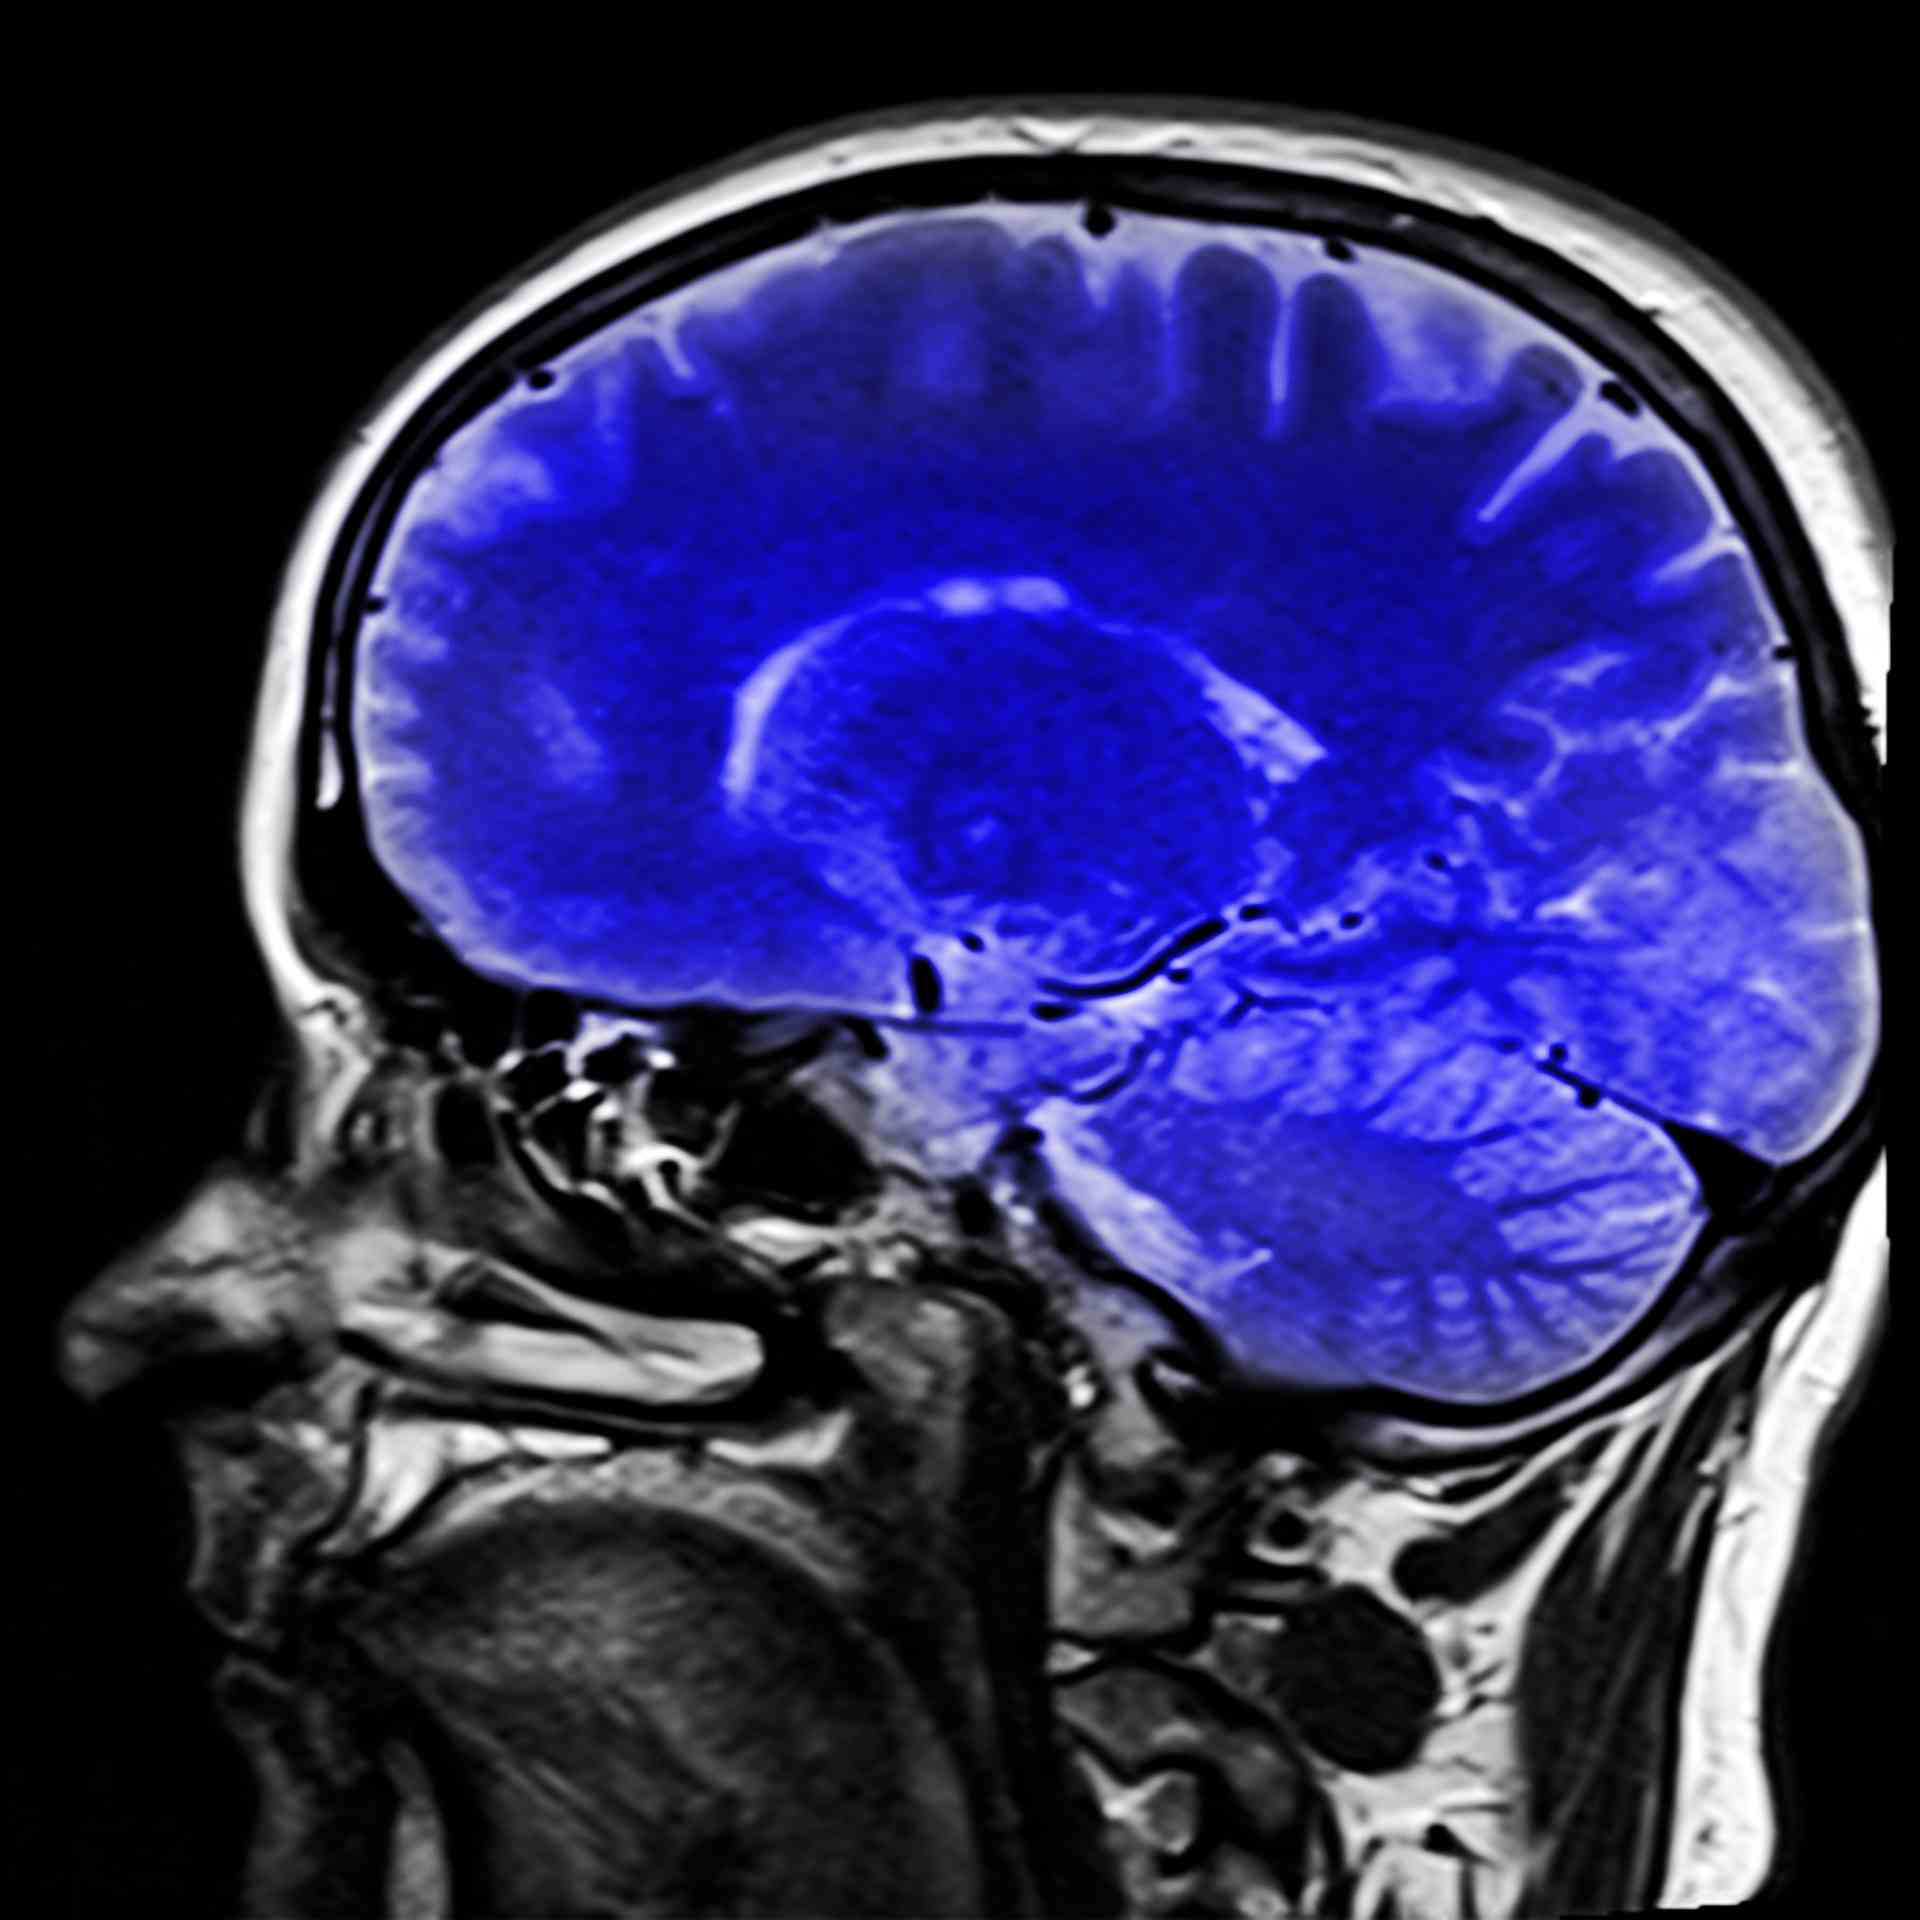

Beyin tümörü olan hasta ne kadar yaşar? Ne Demek Zıt Anlamı Eş Anlamı

Beyin Kanaması Geçiren Hasta Ne Kadar Yaşar Beyin Kanaması Sonuçları